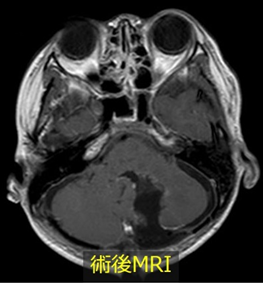

神経細胞を支える役割の神経膠細胞(グリア細胞)の一種である星細胞から発生する腫瘍です。

良性の性格を持つことが多く、大脳や小脳に生じた腫瘍では全摘出することで完治が望めます。しかしながら、脳幹や視床、視神経などに発生した場合には手術が困難であり、放射線治療や化学療法を行なっても治癒困難なことがあります。また、悪性度の高い群も稀にあり、このような場合も放射線治療や化学療法を行いますが治療が難しい疾患の一つです。